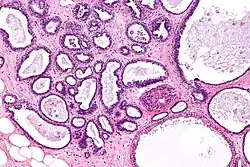

Serous cystadenoma | Histopathology of serous cystadenoma, with admixed scattered ciliated cells. This case closely resembles normal surface endometrial epithelium of the uterus | Category: Histopathology of ovarian serous cystadenoma | Ovarian cystadenoma |

![]() |